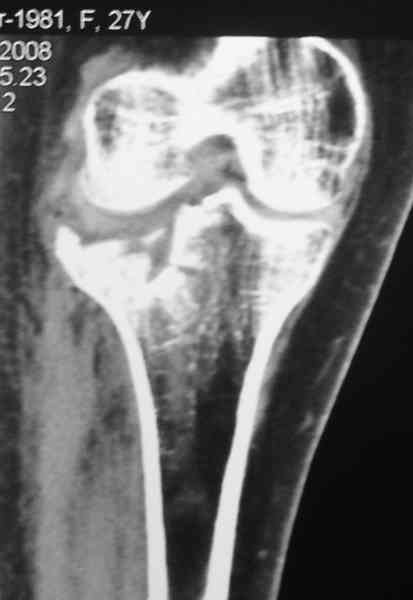

Застарелый перелом 41С3

Обратился больной 46л. 3-месяца назад в каком-то городке Дальнего Востока упал с высоты, сделана Р-графия, наложена гипсовая повязка, от предложенной операции отказался и уехал домой, дальше где и как лечился, не говорит.

Ходит при помощи двух костылей, жалобы на боли при нагрузке, в покое и при движении, без нагрузке боли нет, разгибание 175 гр, сгибание 90 гр, симптомов повреждения связочного аппарата к/с не определяется, от предложенного артродеза пока отказывается.

Уважаемые коллеги! какие будут мнения по поводу лечения, эндопротез недоступен. Заранее благодарю! С уважением Абдурашид.

Уважаемый Абдурашид. Если нет противопоказаний , то из оперативных способов, я бы рекомендовал следующие: Полное замещение наружного мыщелка аллотрансплантатом либо открытая репозиция с элевацией и замещение дефекта ауто или аллокостью. В Ваших условиях , я бы рекомендовал второй способ. Во-время элевации необходимо разъединить фрагменты со стороны сустава ( надсечь скальпелем по линиям перелома, а затем тонким остеотомом их разъединить. При помощи долота произвести неполную остеотомию ( захватите не менее 1,5 - 2 см губчатой кости и поднять фрагменты, визуально отрепонировать и фиксировать 2-3 спицами. Дефект заместить костным ауто или аллатрансплантатом. Окончательная стабилизация пластиной ( лучше с угловой стабильностью, либо АВФ - позволит спокойно устранить угловую деформацию.

Недавно поступила больная через 1,5- 2 месяца.